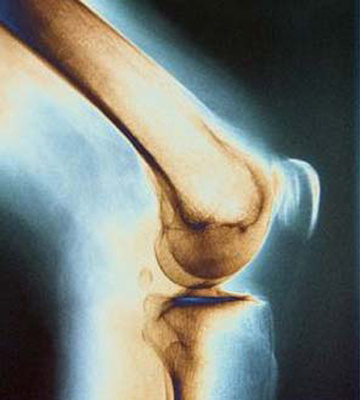

تمرینات تحمل وزن

تمرینات تحمل وزن، حرکات ورزش و فعالیتی است که عضلات را در مقابل جاذبه زمین فعال می کند. تمرینات تحمل وزن به استخوان ها فشار وارد میکند که به بهبود توده استخوانی کمک می کند. برای برخورداری از بیشترین تاثیر این حرکات، تمرینات تحمل وزن بالا توصیه می شود. اما اگر مطمئن نیستید چگونه باید این حرکات را شروع کنید، لازم است با پزشک و فیزیوتراپیست مشورت کنید.